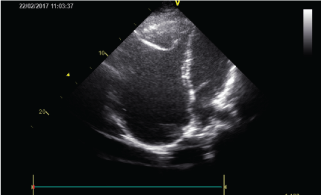

A 24-year-old woman applied to the cardiology department for exercise intolerance. She had been diagnosed and followed up as Ebstein anomaly for ten years. Her heart rate was 75/min with normal jugular venous pressure. Findings of lung examination were normal. Auscultation of heart revealed a 2/6 systolic murmur on the lower left edge of the sternum. On abdominal examination, there was no organomegaly. Arterial Oxygen Saturation (SpO2) was 98%. Electrocardiography (ECG) revealed absence of atrial fibrillation, the rhythm was sinus but there was right axis deviation and right bundle branch block (Figure 1). There was a significant cardiomegaly (cardiothoracic ratio: 0.7) on telecardiography (Figure 2). Echocardiography demonstrated a severely dilated RA measuring 96 mm × 135 mm in four chamber view (Figure 3) and RV pressure was 40 mmHg indirectly calculated by tricuspid valve regurgitation. There was severe tricuspid regurgitation. Since there was no evidence of apical displacement of the tricuspid septal leaflet, Ebstein's anomaly was not considered.

Figure 3: Transthoracic echocardiogram in the four-chamber apical view demonstrating a massively dilated right atrium. View Figure 3